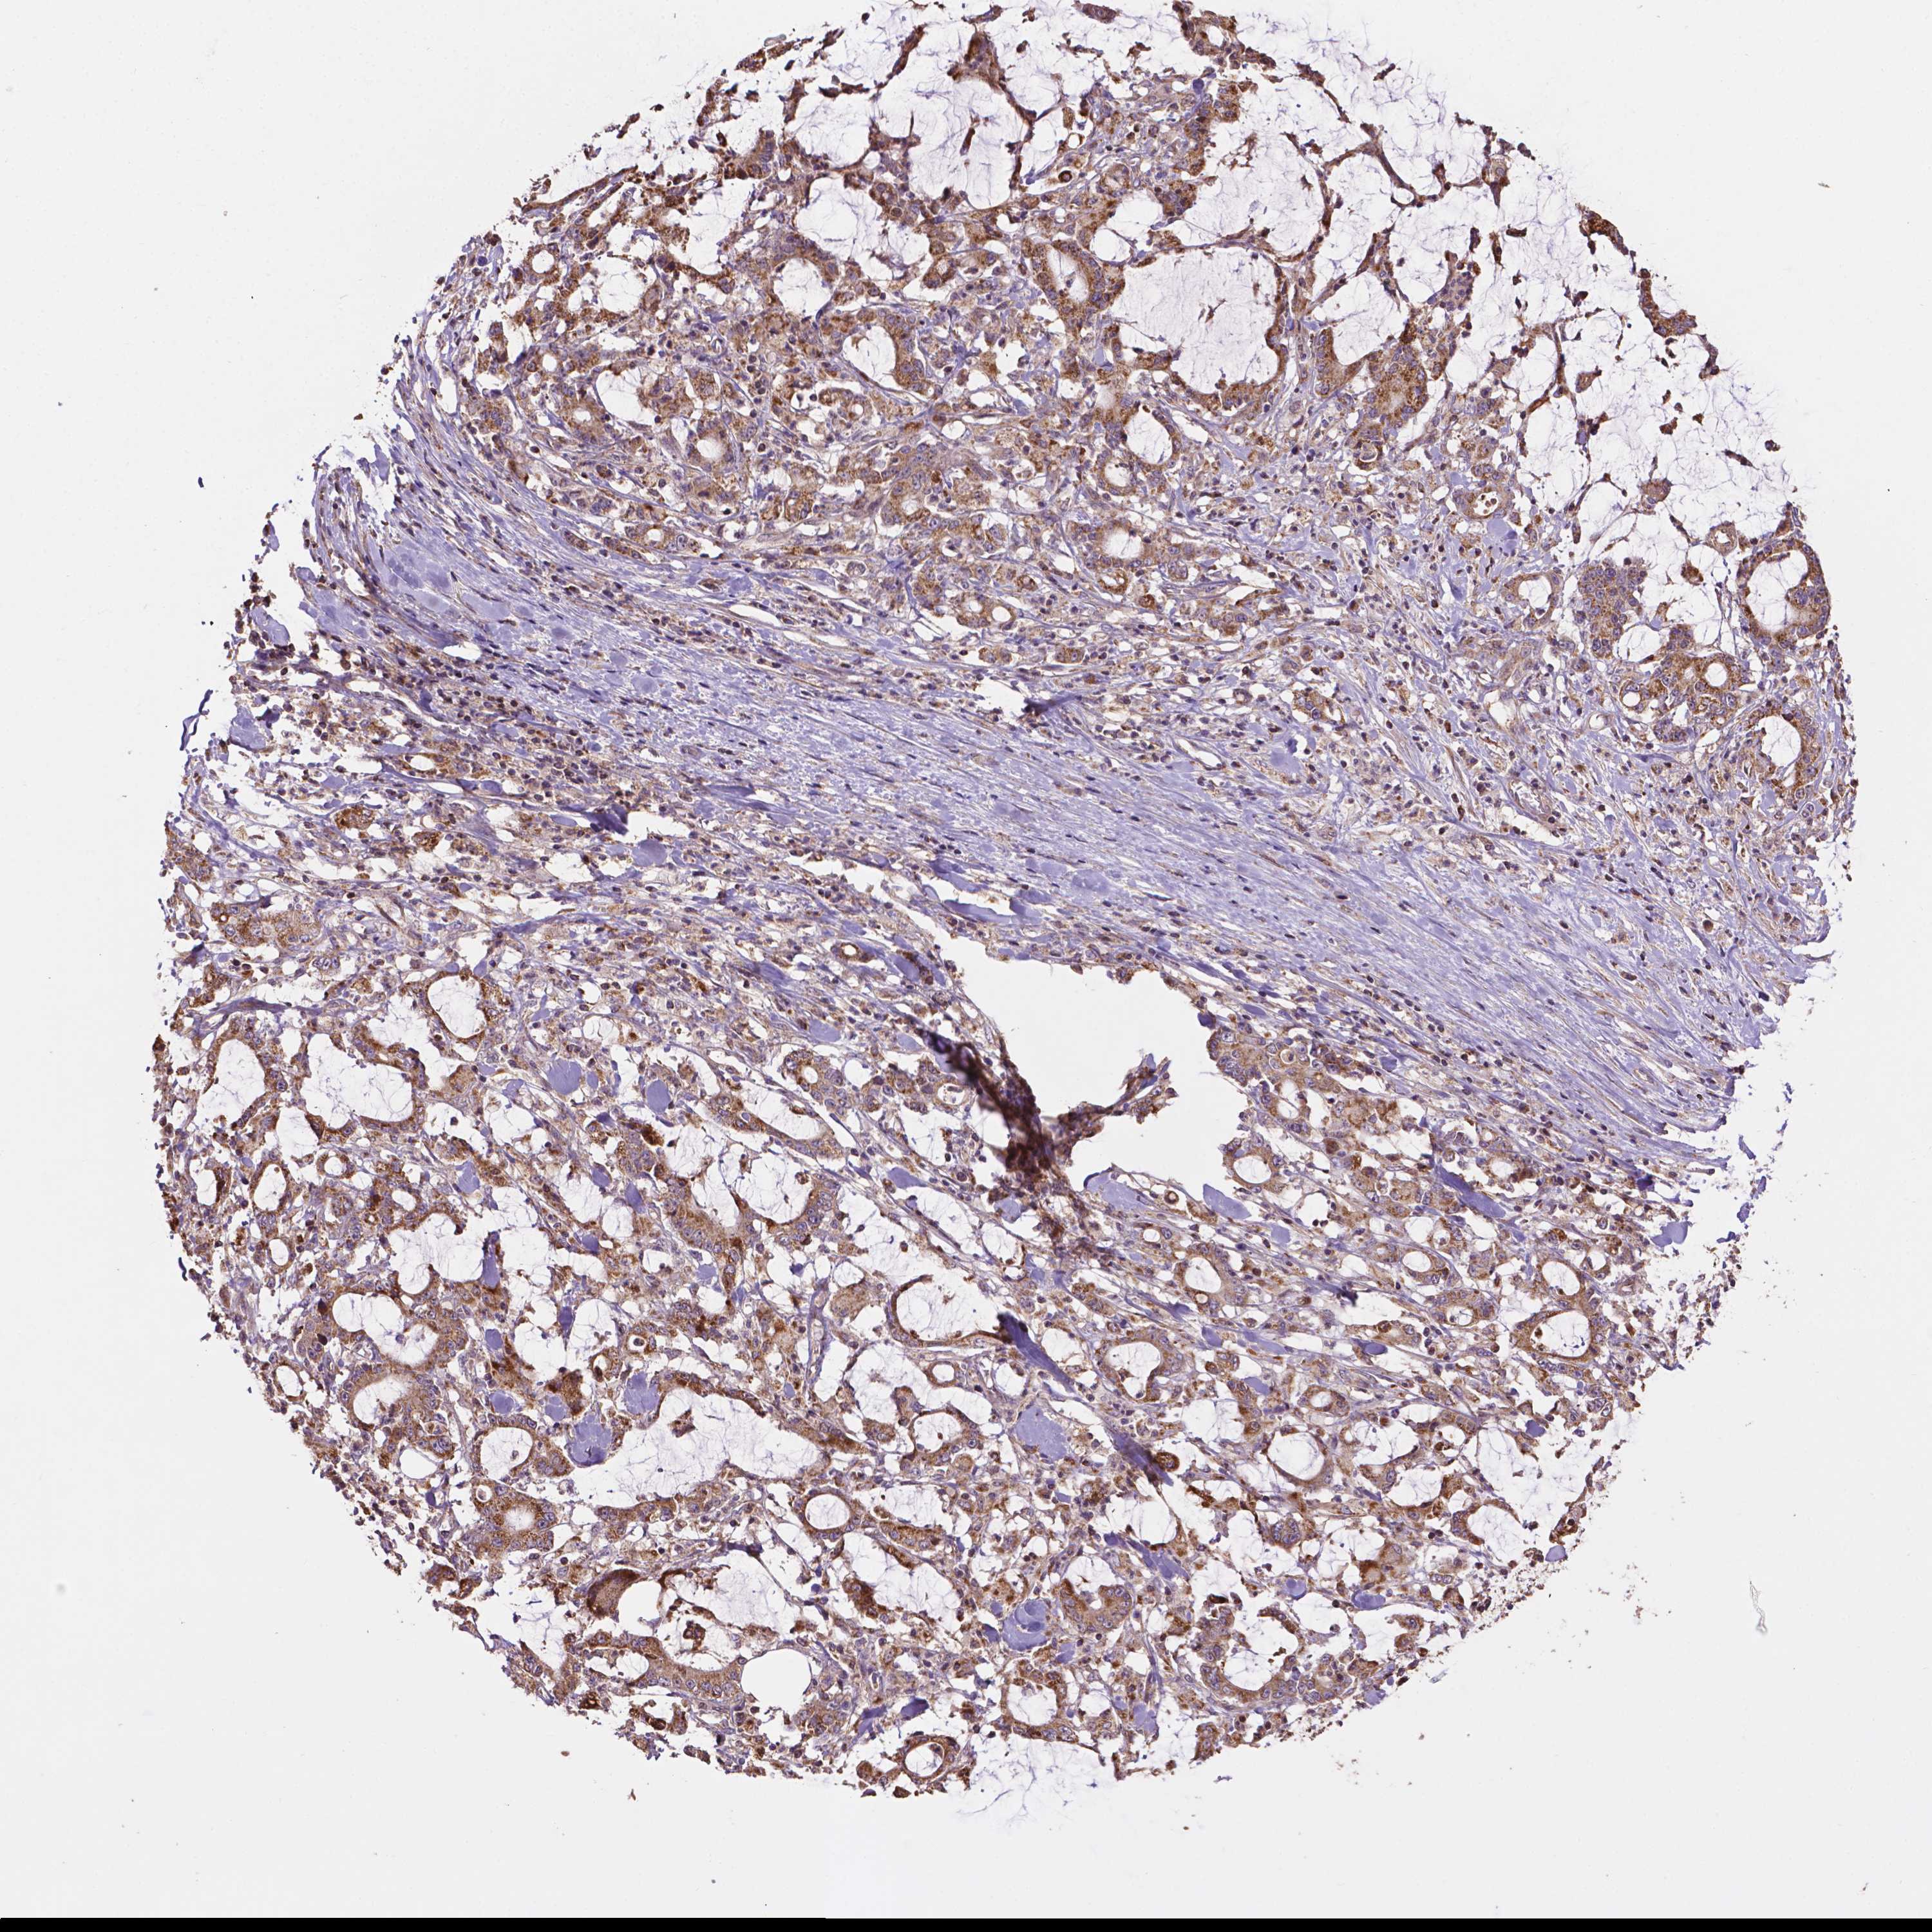

STOMACH CANCER - Protein expressioni

A mouse-over function shows sample information and annotation data. Click on an image to view it in a full screen mode. Samples can be filtered based on level of antibody staining by selecting one or several of the following categories: high, medium, low and not detected. The assay and annotation is described here.

Note that samples used for immunohistochemistry by the Human Protein Atlas do not correspond to samples in the TCGA dataset.

Antibody stainingi

Antibody staining in the annotated cell types in the current human tissue is reported as not detected, low, medium, or high, based on conventional immunohistochemistry profiling in selected tissues. This score is based on the combination of the staining intensity and fraction of stained cells.

Each image is clickable and will lead to virtual microscopy that enables deeper exploration of all samples and also displays staining intensity scores, fraction scores and subcellular localization as well as patient and tissue information for each sample.

Antibody HPA065703

Staining

High

Medium

Low

Not detected

Intensity

Strong

Moderate

Weak

Negative

Quantity

>75%

75%-25%

<25%

None

Location

Nuclear

Cytoplasmic/membranous

Cytoplasmic/membranous,nuclear

Adenocarcinoma, NOS